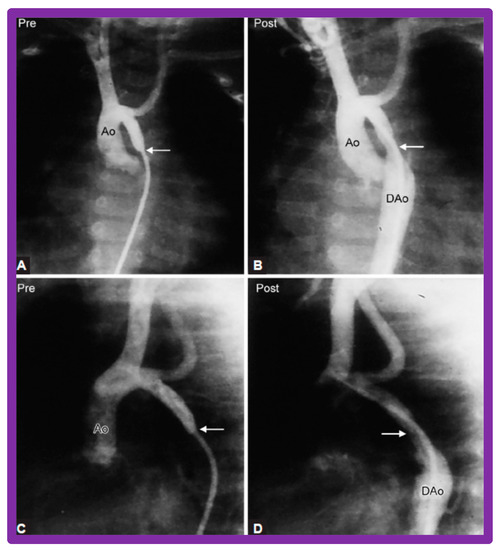

3.3. Aortic Coarctation, Native

4.3. Aortic Coarctation–Native

4.4. Aortic Coarctation, Postsurgical